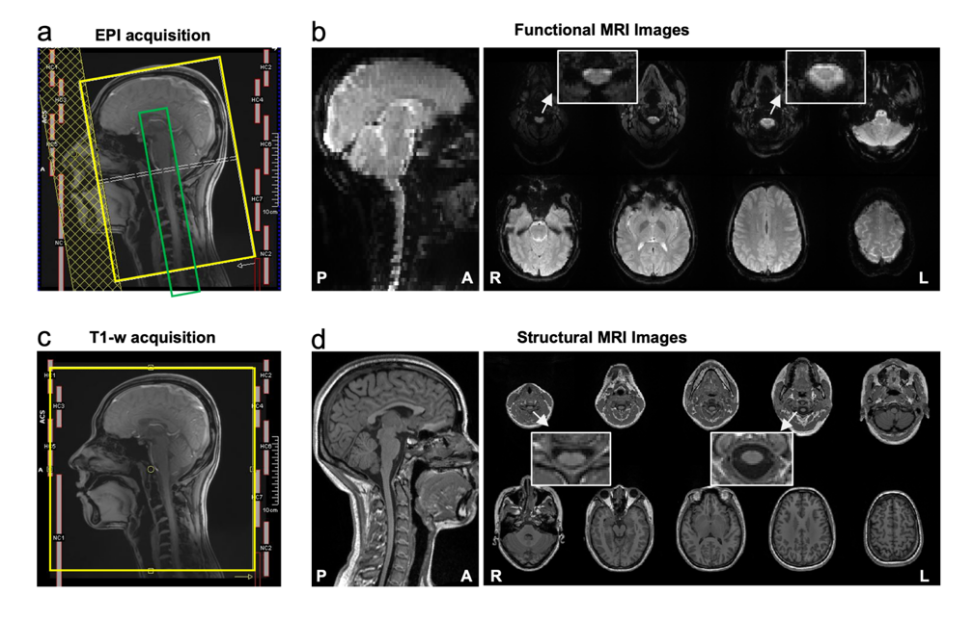

CoSpine成像方案基于西门子 3T Prisma 磁共振系统,实现了覆盖大脑、脑干、小脑及颈段脊髓的单视野同步采集(见图1)。该方案融合多频带并行采集与并行重建算法,在保持1.5毫米高空间分辨率的同时,大幅提升了时间采样效率与图像质量。这一成像策略使皮层—脑干—脊髓神经信号得以在一次扫描中陆续在获取,为系统性研究脑–脊髓功能交互研究奠定了方法学基础。

图1. CoSpine功能与结构成像的采集方案及示意图